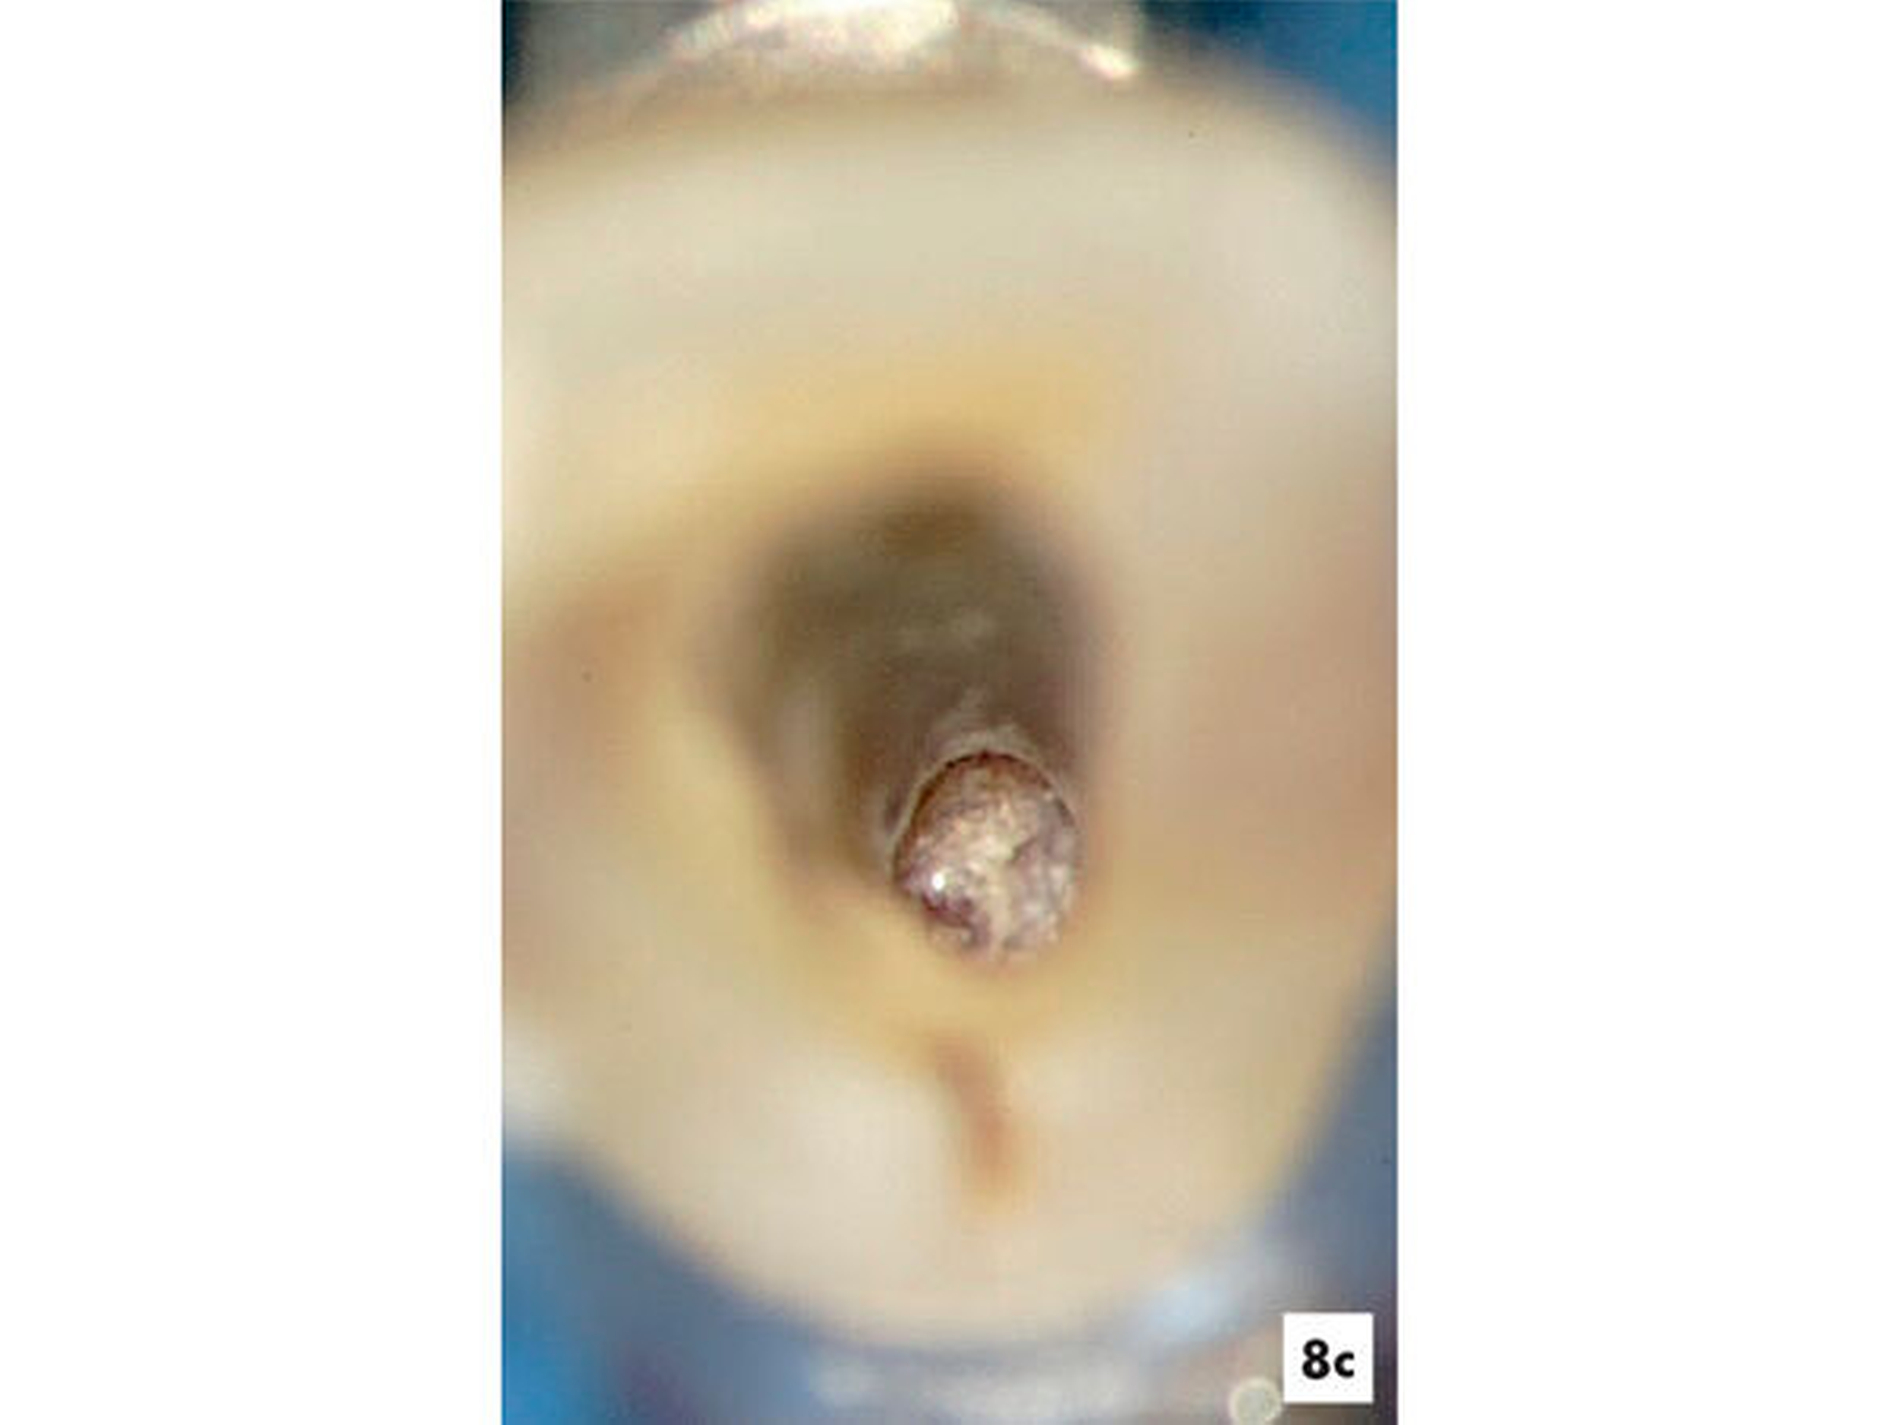

Eine 28-jährige Patientin wurde mit einer Schwellung und Fistel am Zahn 22 in eine auf Endodontie spezialisierte Praxis überwiesen. Die Patientin gab ein drei Jahre zurückliegendes Trauma am Zahn 22 an. Aufgrund des asymptomatischen Verlaufs wurde bisher keine Therapie erforderlich. Der Zahn wies keine pathologischen Sondierungswerte auf und reagierte nicht auf den thermischen und elektrischen Sensibilitätstest. Radiologisch konnte der Fistelverlauf zur lateralen Aufhellung nachgewiesen werden. Innerhalb des Wurzelkanals ließen sich rundliche Erweiterungen erkennen (Abbildung 8a). Es bestand der Verdacht auf eine infizierte Pulpanekrose mit interner Resorption. Im Verlauf der intrakoronalen Befundaufnahme konnte nach Entfernung des nekrotischen Pulpagewebes durchblutetes und sensibel reagierendes Gewebe bei 16-facher Vergrößerung ermittelt werden (Abbildung 8b). Es bestand das Ziel, die bakterielle Infektion zu eliminieren und das vitale Gewebe zu erhalten und zu einer Reparatur der resorptiven Defekte anzuregen.

Fallbeispiel 6: Reparatur einer internen Resorption

Nach einer mechanischen Erweiterung des koronalen Wurzelkanals und Desinfektion mit NaOCl in 3-prozentiger Konzentration wurde für einen Zeitraum von sechs Wochen frisch angemischtes Ca(OH)2 genutzt, um das Dentin zu desinfizieren. Im Anschluss wurde das Dentin mit 17-prozentiger EDTA-Lösung gespült und eine Blutung induziert, damit der gesamte resorptive Zahnhartsubstanzdefekt mit Ersatzgewebe gefüllt werden konnte (Abbildungen 8c und 8d). Das Blutkoagel wurde mit MTA abgedeckt und die Kavität mit Komposit zur Vermeidung einer Reinfektion verschlossen.